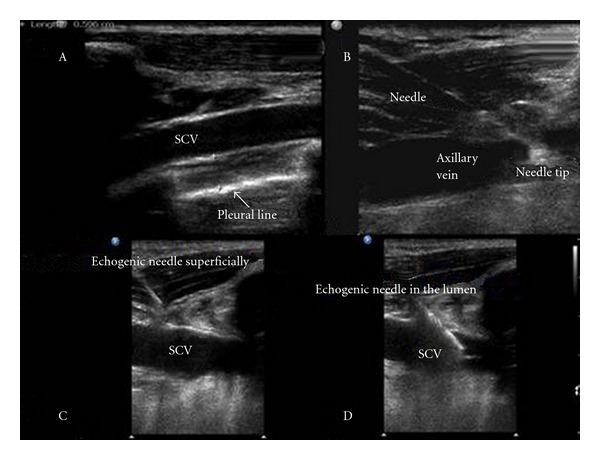

Short-axis (cross-sectional, transverse) ultrasound view를 선택하는 방법이 subclavian vein(쇄골하 정맥)과 subclavian artery(쇄골하 동맥)의 위치를 확인하는데 더 유리하다. 화면에서 echogenic(eg, white) dot로 나타나는 바늘 끝은 앞뒤로 움직일 때 화면에서 사라지기도 하고 다시 나타나기도 하므로, cross-section에서 천자한 바늘 끝을 확인하는 데에는 약간의 기술이 필요하다. 보통 short-axis view는 적절한 vein 위치를 결정하고 45' 이상의 가파른 각도로 바늘을 삽입할 때 사용할 수 있다.

Long-axis (longitudinal, in-plane) ultrasound view는 probe를 고정해야 하고 vein과 바늘을 한 화면에 보이게 해야 하므로 기술적으로 더 어렵다. 하지만 바늘을 종적(longitudinal)으로 보여주므로 바늘 끝을 포함한 바늘 전체를 시술 과정에서 화면에서 연속적으로 볼 수 있어서 바늘이 잘못 위치하게 되는 위험을 줄여주는 장점이 있다. Long-axis view는 바늘 삽입 각도가 얕을 때 유용하며(eg, axillary/ subclavian cannulation), short-axis 삽입 후 바늘이 혈관 안에서 적절히 종적으로 위치하고 있는지 확인할 수 있다(target sign).